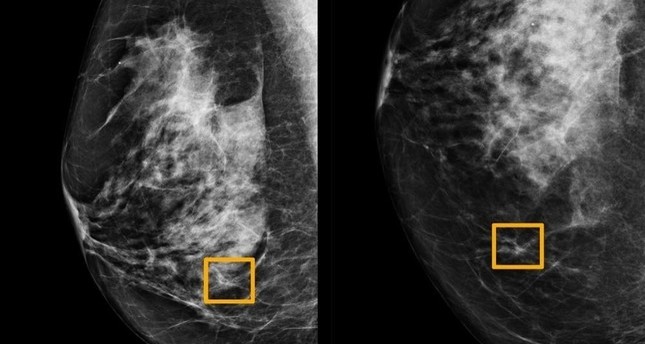

تقنية جديدة تسه ل عملية الكشف عن سرطان الثدي Swi Swissinfo Ch

الذكاء الصناعي يكشف أورام الثدي التي لا يميزها الأطباء Daily Sabah Arabic